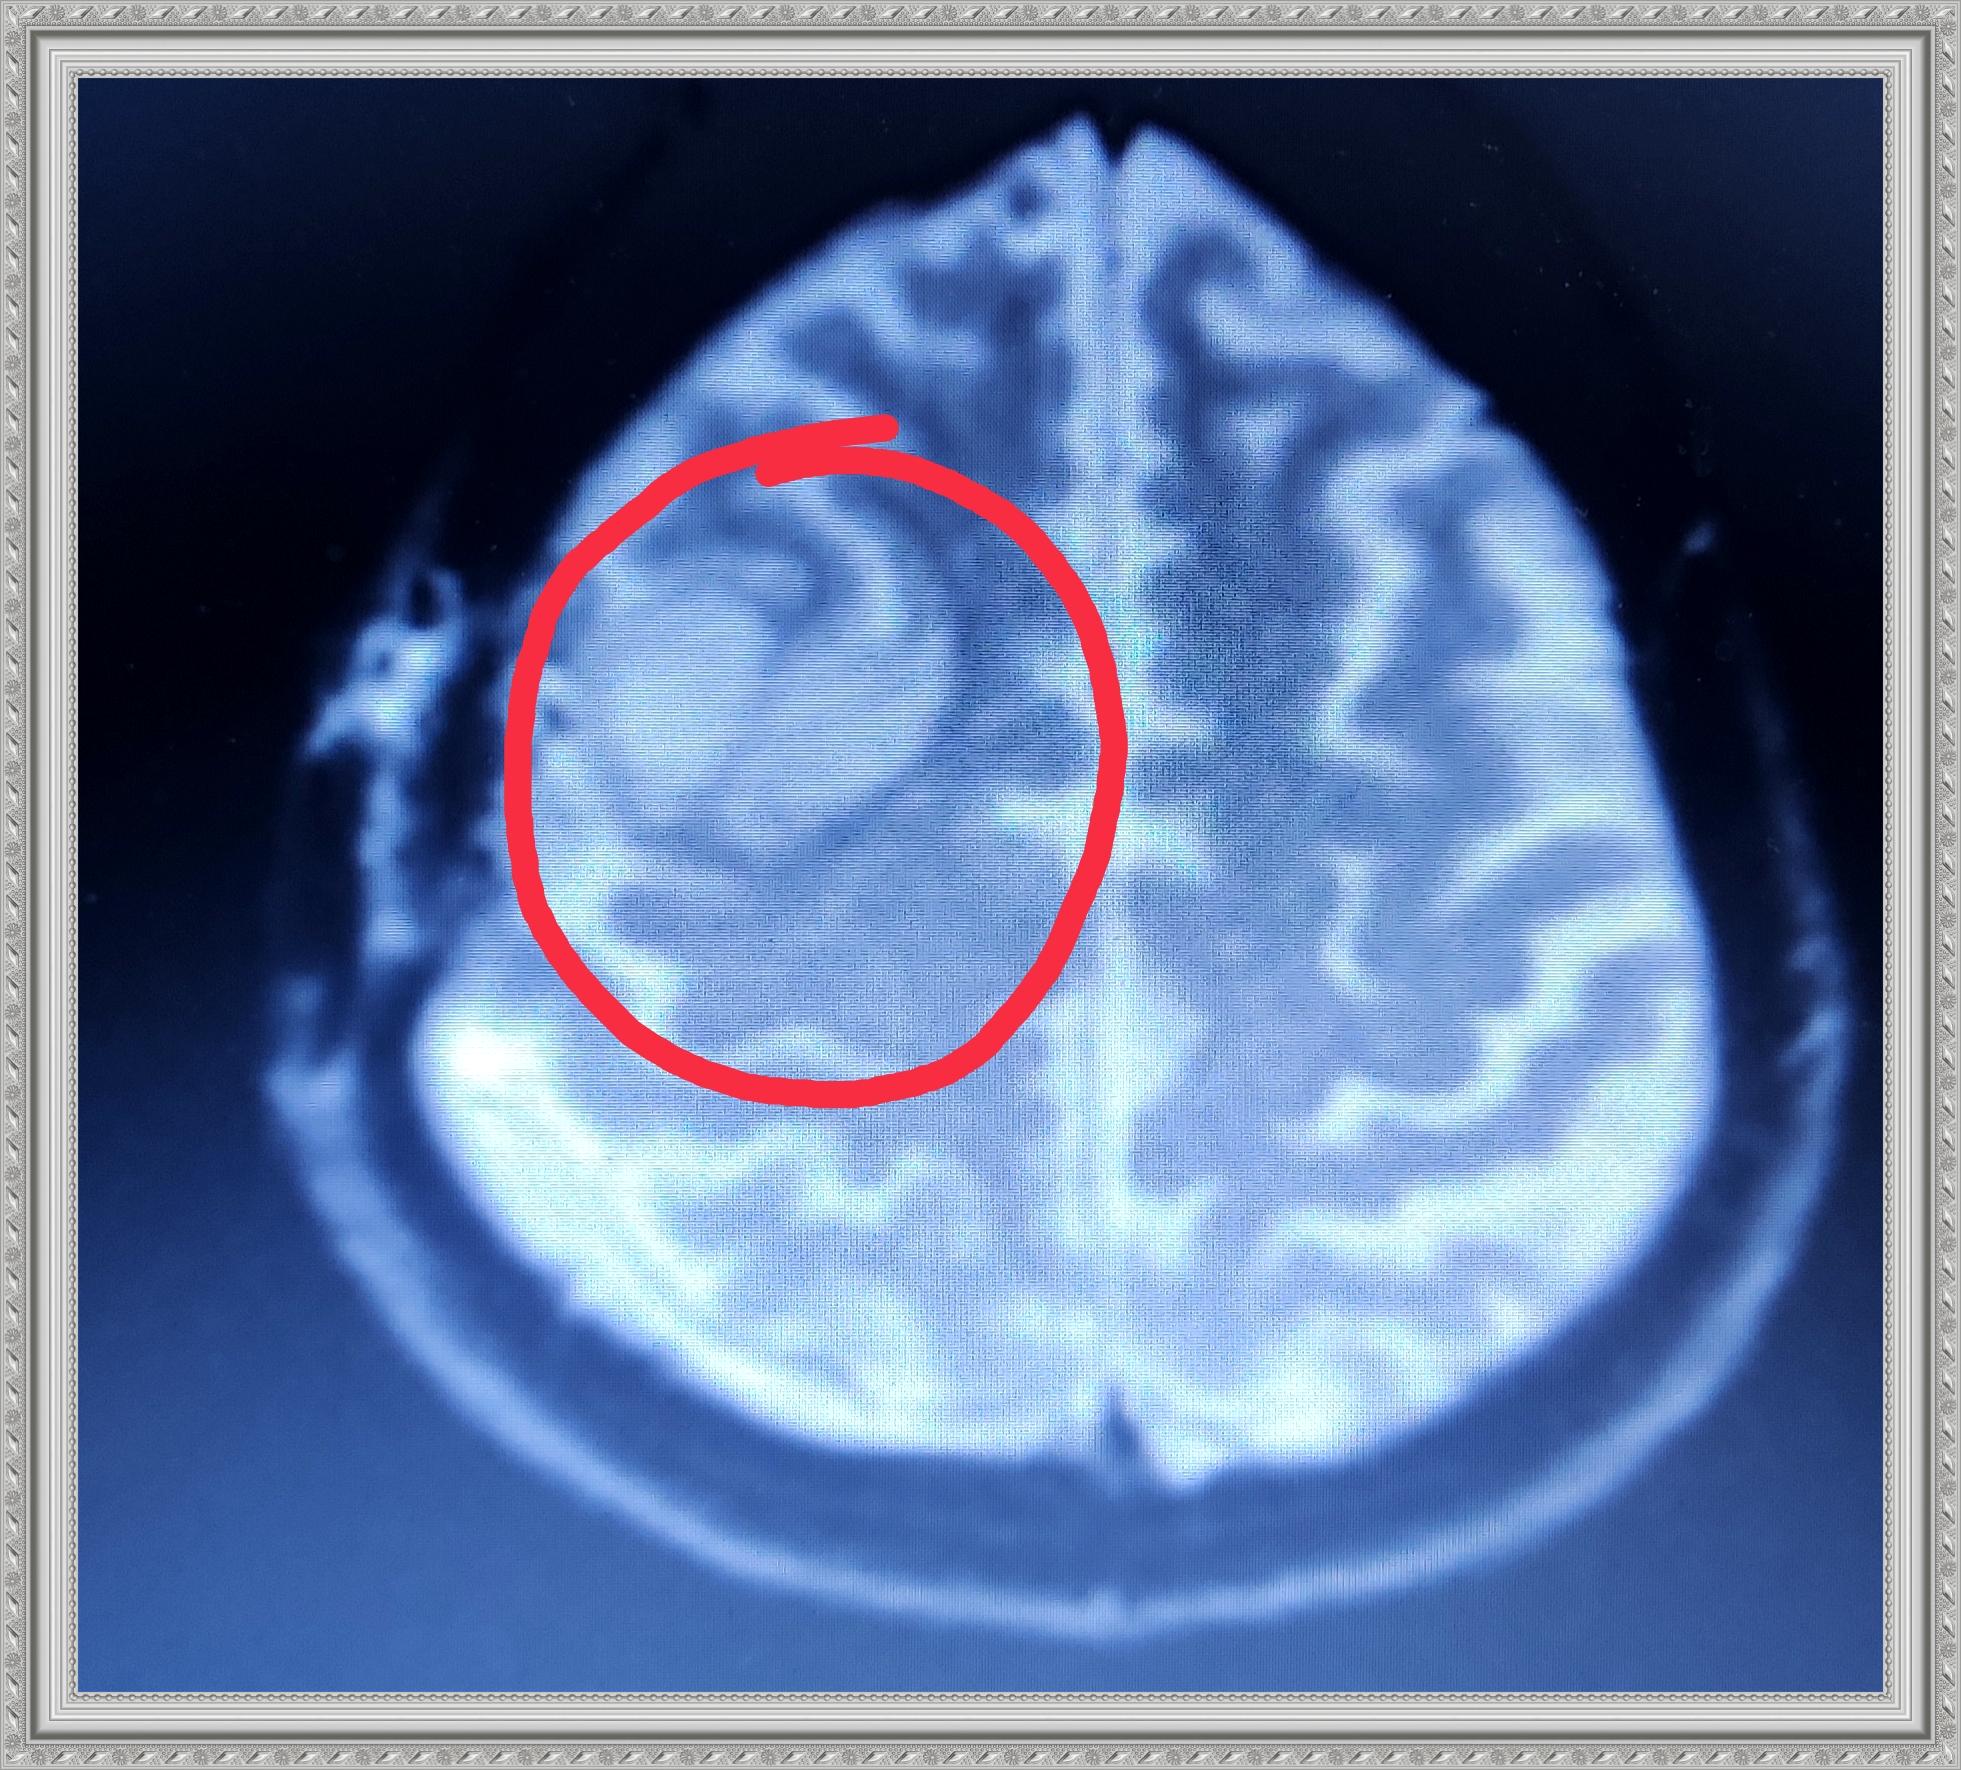

The next gallery shows me at Memorial Central Hospital in Colorado Springs after having surgery to remove my tumor and staying for a few weeks after for Physical, Speech and Occupational Therapy. The staff there was so AWESOME! I hold every one of them dear to my heart.